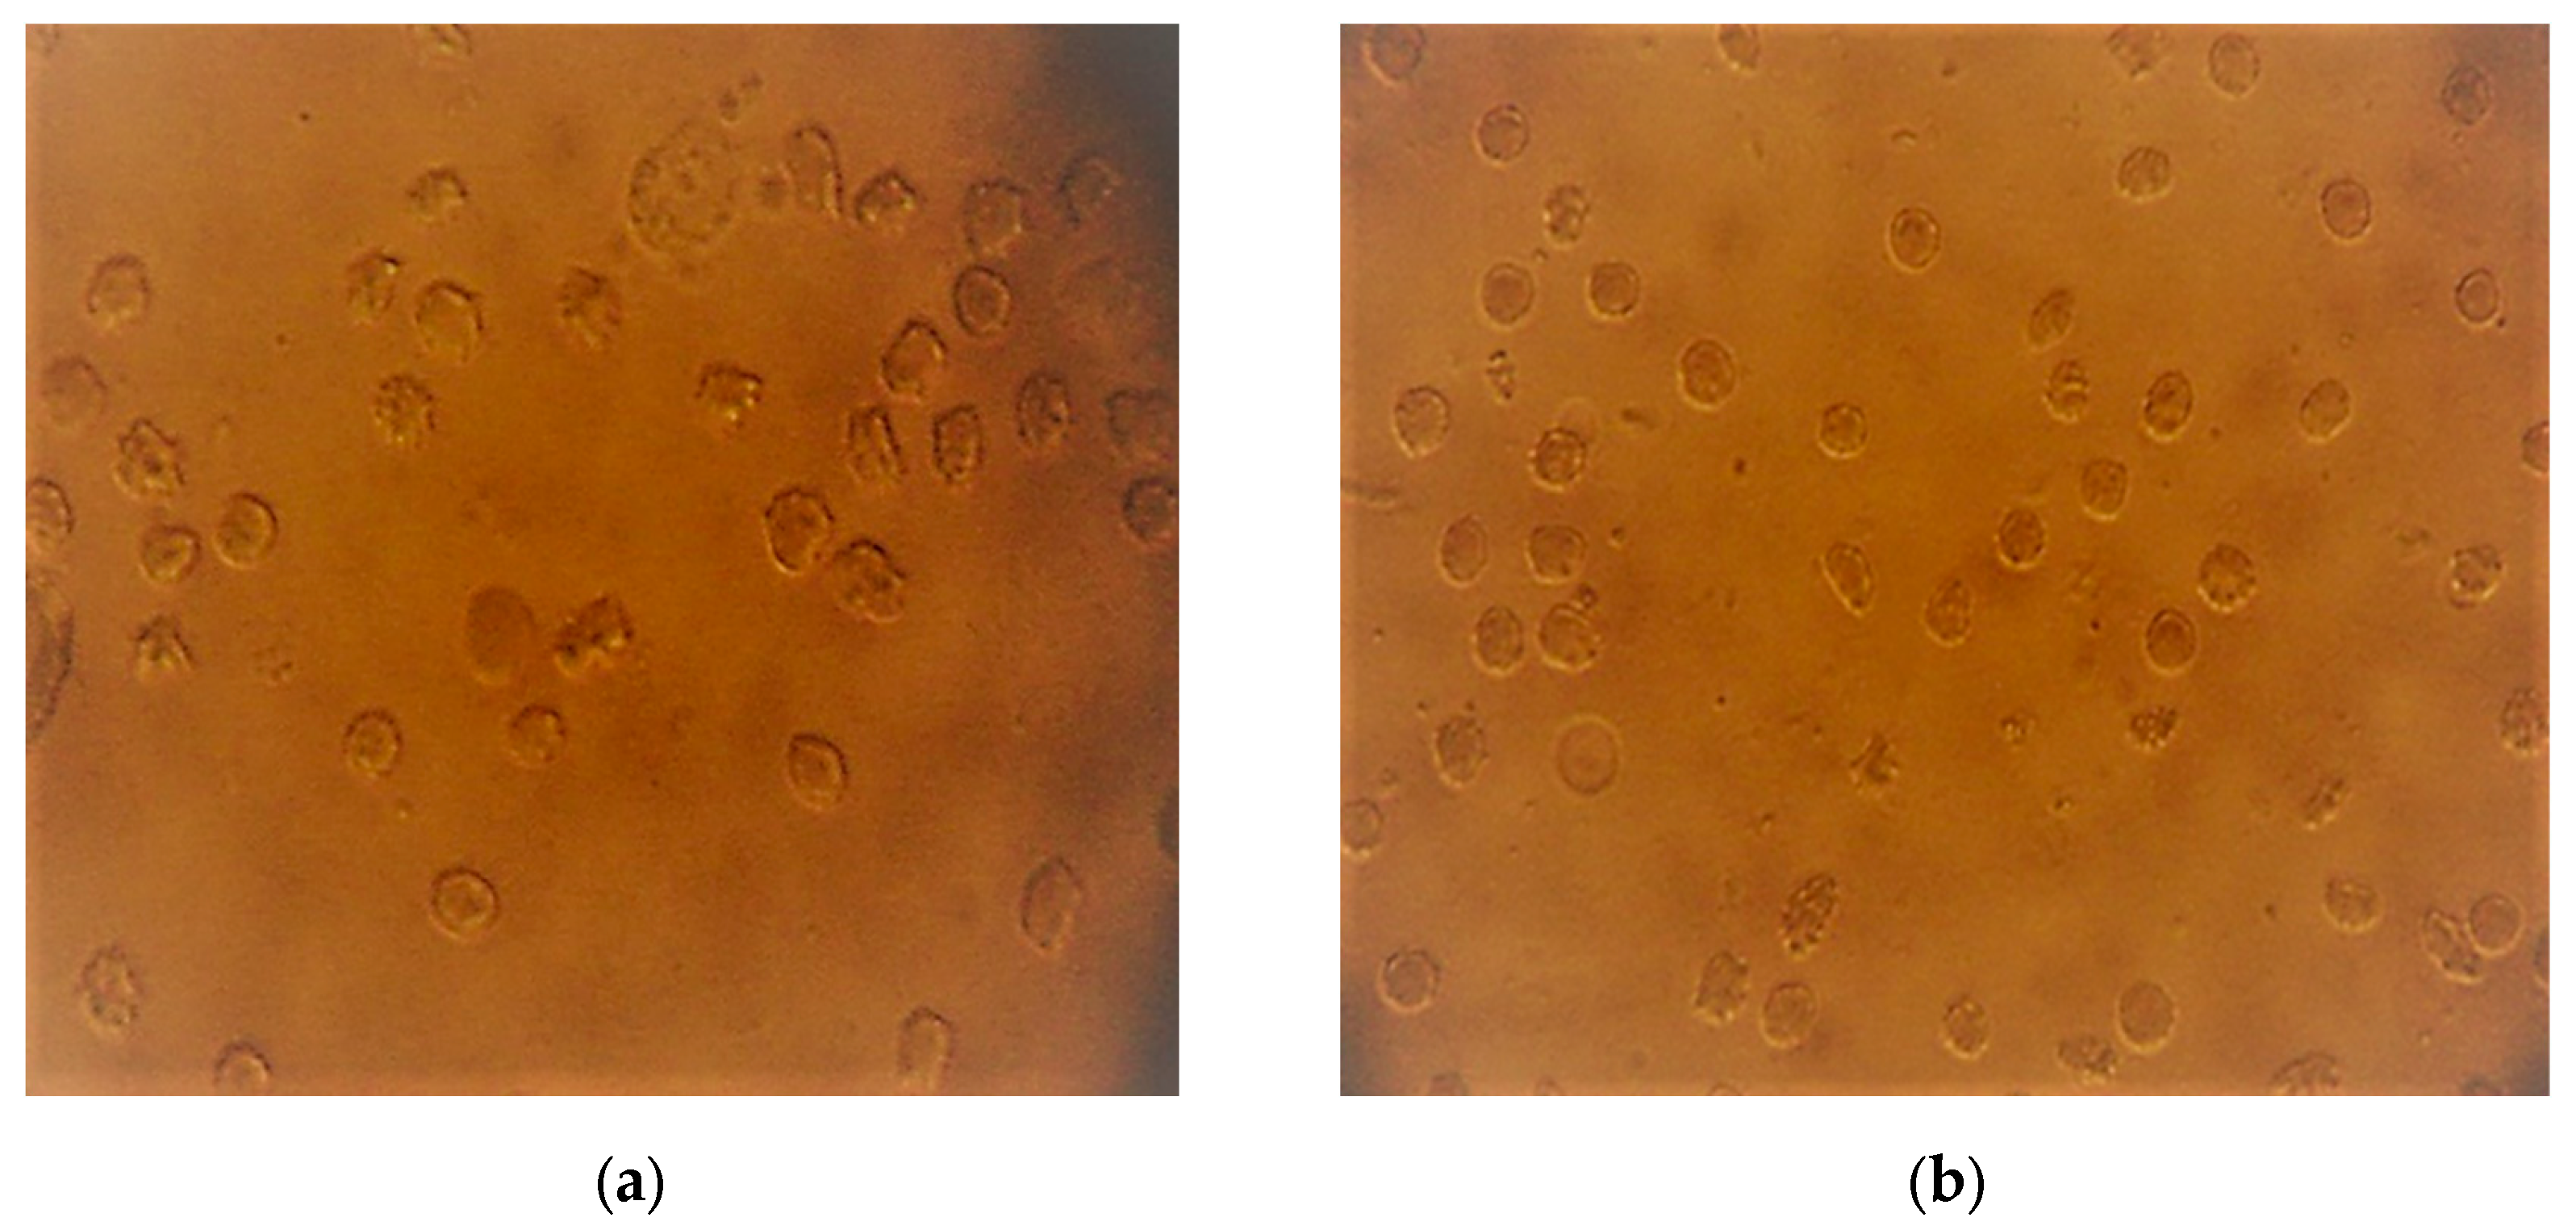

| Plants | Type of Extract | Rate of Normalization |

|---|---|---|

| Flueggea virosa (Rxb. ex Wild.) Voigt | Aqueous | 90% |

| Ethanolic | 95% | |

| Kigelia africana (Lam.) Benth. | Aqueous | 85% |

| Ethanolic | 93% |